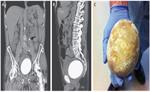

پێشکەوتنی گەورە لە پزیشکیدا؛ چارەسەری نوێ بۆ دڵ و دووگیانی و چاندنی ئەندامەکان